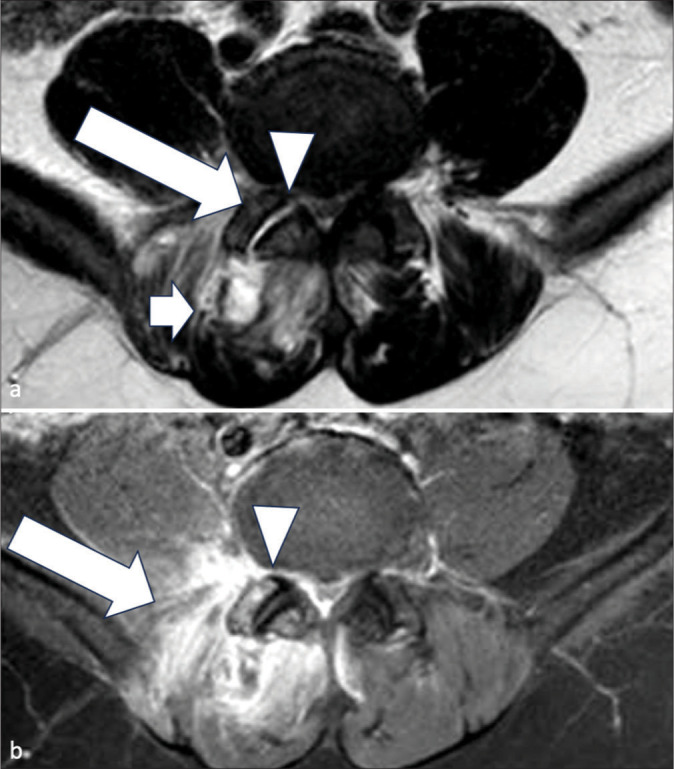

面关节化脓性关节炎是一种罕见的严重脊柱感染,但由于其临床表现和影像学表现不特异,常常被误诊。本系列病例展示了面关节化脓性关节炎患者的各种临床表现、影像学特征和预后。我们展示了不同的疾病分期,以帮助临床医生和放射科医生识别这种疾病。同时还讨论了关键的诊断误区,以提高临床实践中诊断的准确性。

Facet joint septic arthritis is a rare; yet, severe spinal infection often misdiagnosed due to its non-specific clinical presentation and radiological mimickers. This case series illustrates various clinical presentations, imaging features, and outcomes of patients with facet joint septic arthritis. We demonstrate different disease stages to aid clinicians and radiologists in recognizing this condition. Key diagnostic pitfalls are also discussed to enhance diagnostic accuracy in clinical practice.